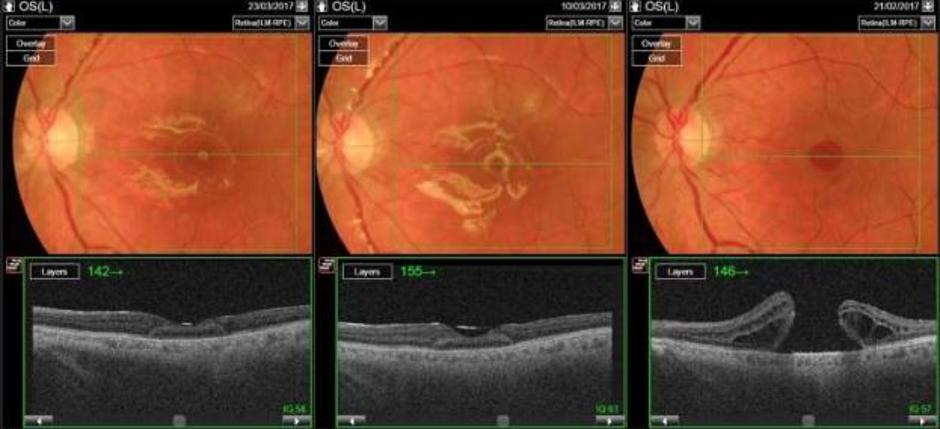

Z očesne klinike Univerzitetnega kliničnega centra (UKCLJ) so sporočili, da so konec februarja uspešno opravili avtologno presaditev mrežnice. Kot so pojasnili, gre za inovativen poseg, saj jih je bilo do sedaj po svetu opravljenih le dvajset.

Operacijo je vodil priznani vitreoretinalni kirurg Xhevat Lumi, ki sicer na očesni kliniki UKC Ljubljana deluje že dve desetletji. Kot je pojasnil, pri tovrstnem posegu presadijo del zdrave mrežnice.

Inovativno operacijo so izvedli pri bolniku z veliko luknjo v rumeni pegi, ki se s standardnim operativnim pristopom ni zaprla.

Po pojasnilih zdravnika se med operacijo del zdrave mrežnice s periferije presadi na mesto manjkajoče mrežnice v rumeni pegi. "V nasprotju z dozdajšnjimi razmišljanji namreč, da se mrežnica kot živčno tkivo ne da presaditi, te začetne izkušnje kažejo, da se presajena mrežnica čez čas vendar zaraste in integrira v novem okolju ter postopoma prevzema svojo funkcijo," je dejal Xhevat Lumi, ki je od leta 2008 tudi vodja oddelka za kirurgijo na omenjeni kliniki.

Dober mesec po operaciji so rezultati pri bolniku po navedbah Lumija zelo obetavni. Luknja se je s pomočjo presadka mrežnice zaprla, prišlo je tudi že do rahlega izboljšanja vidne ostrine operiranega bolnika.